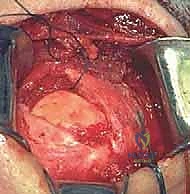

يُجري الجراح شقاً جراحياً دقيقاً (حوالي 5 إلى 7 سم) فوق مفصل الكتف. يتم فصل ألياف العضلة الدالية (Deltoid) بعناية فائقة للوصول إلى الكفة المدورة دون إتلاف العضلات السطحية.

المرحلة الثانية: تجميل الأخرم (Acromioplasty) وإزالة الضغط

قبل إصلاح الوتر، يجب معالجة سبب التمزق. يقوم الدكتور هطيف بإزالة الجراب الملتهب (Bursa) الذي يسبب الألم. ثم يستخدم أدوات دقيقة لإزالة النتوءات العظمية من أسفل عظمة الأخرم، مما يوسع المساحة ويمنع احتكاك الوتر المُصلح لاحقاً.

في حالات التمزقات الضخمة، قد تكون الأوتار متراجعة وملاصقة للعظم ومغطاة بالتليفات. هنا تبرز أهمية الجراحة المفتوحة، حيث يتم تحرير الأوتار بعناية فائقة وإعادتها إلى مرونتها الطبيعية لتصل إلى مكان تثبيتها الأصلي دون شد مفرط.